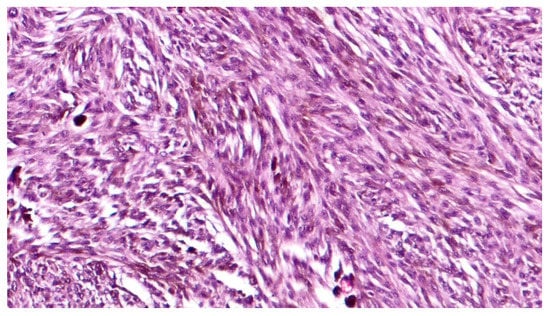

3. Histopathological Features

4. Immunohistochemical Features